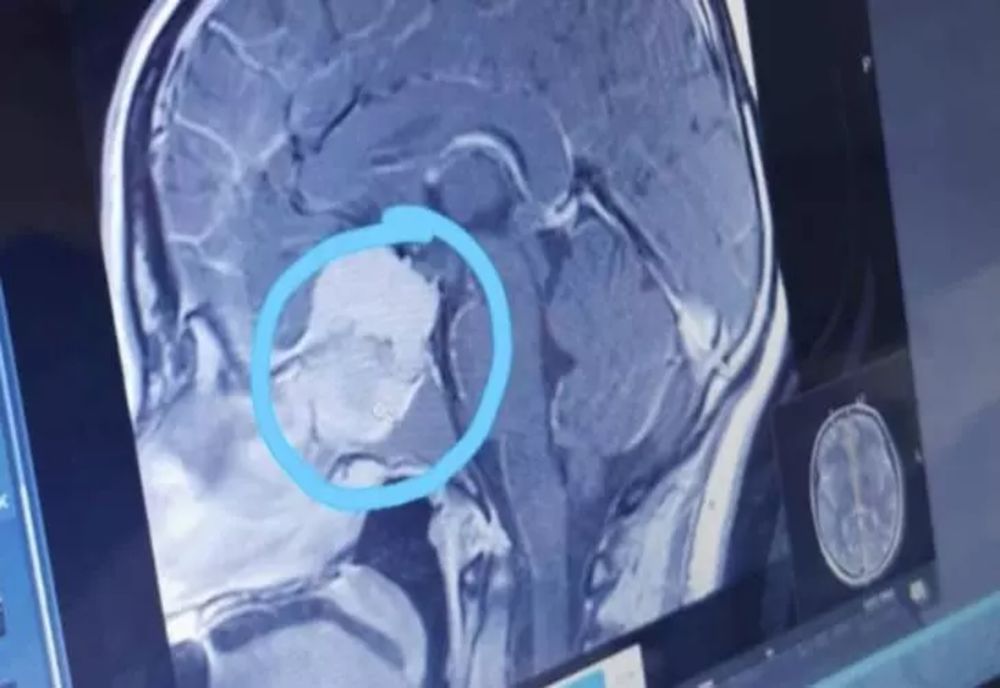

19 mai 2023, 12:21ActualitateUn angajat al spitalului din Piatra-Neamț a făcut AVC la muncă! A fost salvat de medicii din Suceava

14 mar. 2023, 08:07ActualitatePersoanele cu această grupă de sânge au cel mai mare risc de accident vascular cerebral